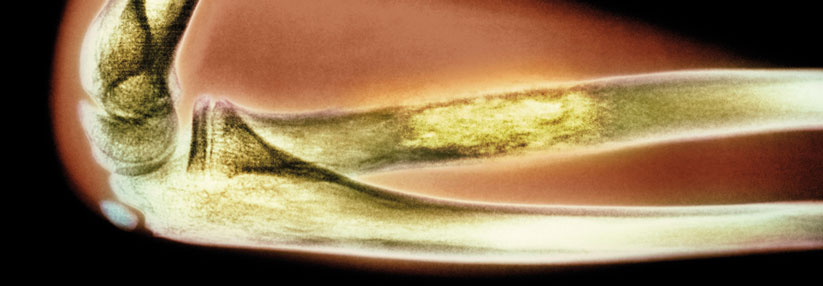

Vier der acht Patienten, die das Team auswertete, wiesen eine stabile Krebserkrankung auf. Vier der acht Patienten, die das Team auswertete, wiesen eine stabile Krebserkrankung auf. © iStock/vitanovski